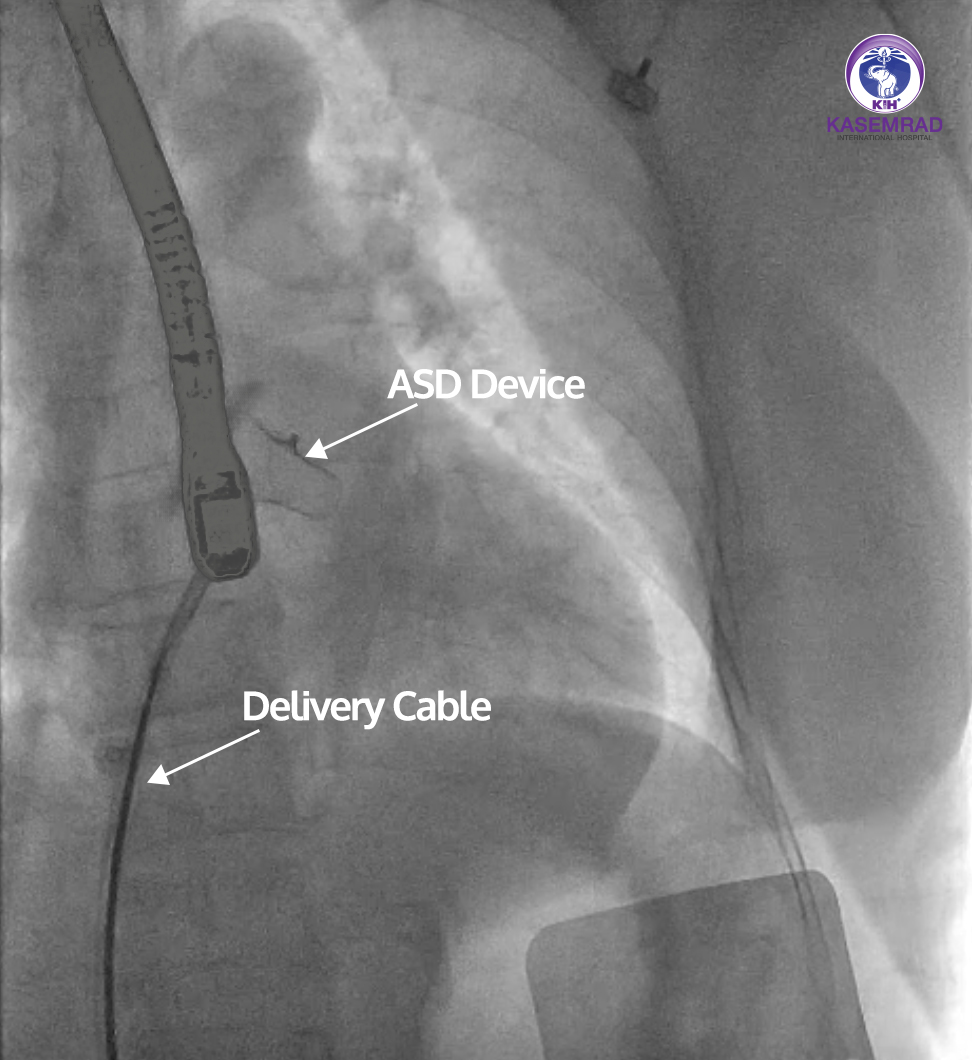

Success Achieved! Last week, our team of expert cardiologists successfully performed ASD Closure (Atrial Septal Defect Closure) using the Transcatheter ASD device closure. This advanced procedure eliminates the need for open-heart surgery by placing a specialized device through a catheter.